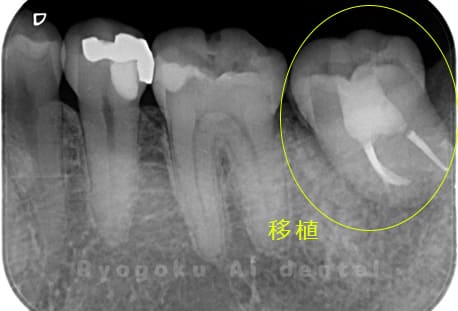

他院で右下の根の治療を行い、セラミックを被せる説明をされていたが、根の治療が終わらないため転院された患者さんです。隣の親知らずの抜歯の必要性と、根の治療を行なっている歯牙の予後が悪いため、移植治療を提案し、右下の親知らずの抜歯と同時に、右下の奥歯(7番)への移植治療を行いました。被せ物を行う必要もなく、順調に経過してます。